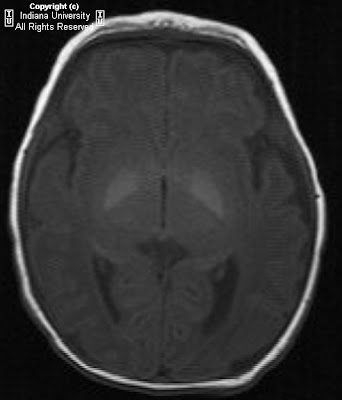

Figure 1: On the right, the mastoid air cells are under pneumatized. There is no identifiable external auditory canal.

Figure 2: A thick bony plate is visualized in the expected area of the external auditory meatus.

Figure 3: The facial nerve is identified.

Figure 4: There is a small amount of bone in the attic of the middle ear cavity but no formed malleus or incus is identified. This suggests rudimentary and/or hypoplastic ossicles. However, a normal morphology and location of the stapes is seen. The internal auditory canal is normal in caliber.

Figure 5: The apical and basal turns of the cochlea are within normal limits.